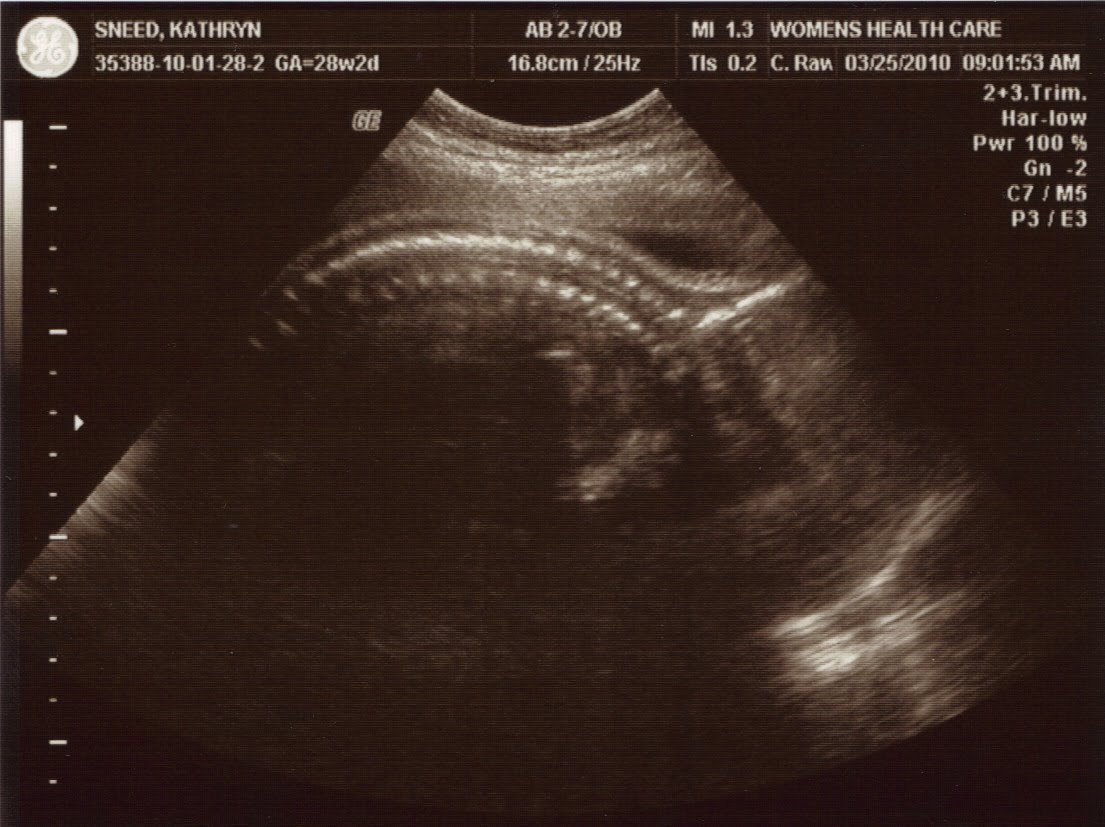

We got to the Doctor’s at 8:45 and waited only a few minutes before they called me for my ultrasound. The reason for this ultrasound was to check something in his heart that they had seen in the ultrasound at 20 weeks. Everything looked great, and they said it was fine. We got to see all four chambers of his heart and she said it looked good!

Adam weighs 2lbs. 12oz. and he has hair!! They showed us his leg bone, and said he is going to be tall! Just like his daddy! (Jon is 6 feet 1 inch.) I am 28 weeks 2 days, but he is measuring about 1 week ahead!